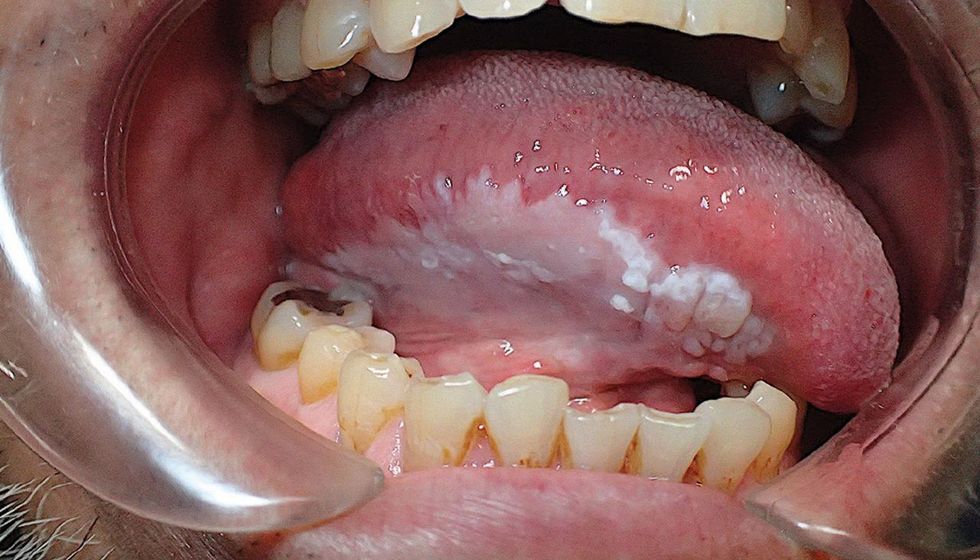

Ngjyra e bardhë në gjuhë mund të shfaqet edhe tek leukoplakia – gjendje për shkak të së cilës krijohen njolla të bardha në gavrën e gojës. Fjala është për plagët të cilat ndonjëherë mund të paraqesin fillim të karcinomës, theksojnë ekspertët. /Telegrafi/